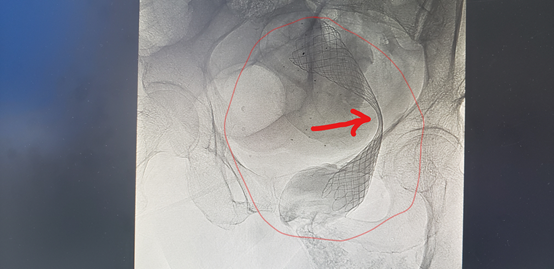

▲红圈就是李医生放置的支架,箭头所指的方向

就是因为肿瘤压迫而造成的“蜂腰”征

红圈内支架也已经完成撑开